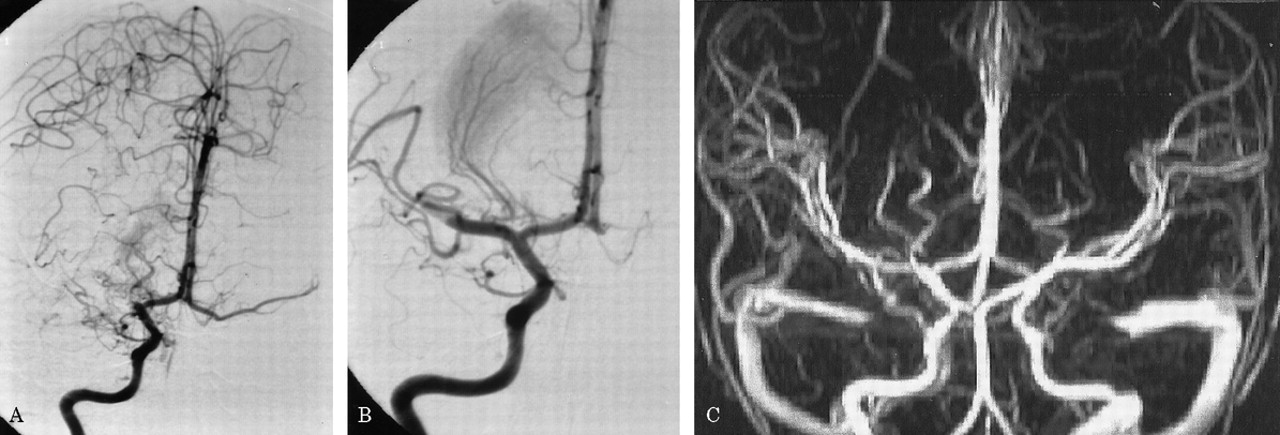

我们的病人,手术后神经完好,有阵发性发作,其中涉及左胳膊和腿术后48小时。发作停止在5分钟内,随后postictal意识障碍,左面部神经麻痹,左半身不遂。因为这些赤字没有开始发病60分钟内解决,头部CT扫描。这些CT扫描未能证明急性脑缺血的早期迹象,但积极披露”中签署“正确的MCA干线(图1一个)。血管造影进行120分钟后出现了MCA闭塞(图2一个)。使用一个施行,guidewire-controlled flow-independent microcatheter(成功之路10;波士顿科学/目标疗法,弗里蒙特,CA)是采用通过15 f造影导管引入正确的MCA干线。microcatheter当时先进的进一步允许选择性与导管尖端嵌入到血栓点燃。选择性应用2.5毫克rTPA(0.11毫克/公斤体重)重复小丸和机械破坏的凝块导导致血管再通的MCA领土(图2中,B和C症状出现后150分钟。CT扫描获得之后没有显示颅内出血的迹象,和胸部x射线显示缺乏心包积血。

图1所示。(A)术前CT扫描显示积极的高密度的大脑中动脉(MCA)标志正确的MCA干线。(B)术后t2加权MRI 2周后动脉内的溶菌作用显示正常流动孔隙MCA干线,也是纹状体梗塞影响壳核和尾状核,保留内部胶囊。

图2。(一)右颈内动脉血管造影披露血栓栓塞大脑中动脉(MCA)阻塞。(B)血管造影在动脉内的溶解(约20分钟后血管造影获得2 a所示)显示了MCA干线的血管再通和纹状体外动脉增外侧。(C) Postinterventional MR血管造影显示血管再通整个MCA的领土。